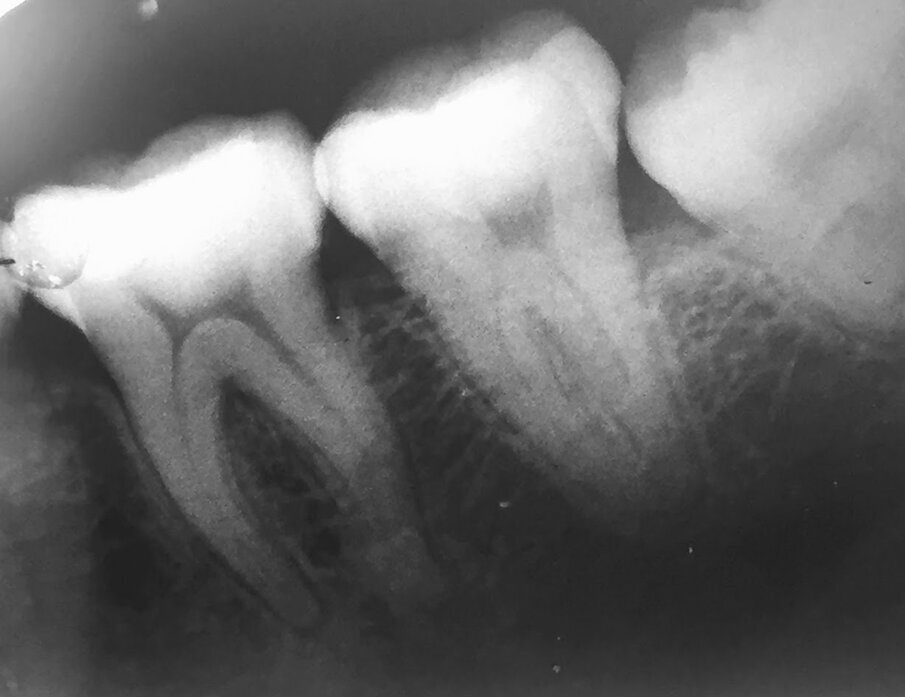

Dr Margaret Tui, a clinician based in the Philippines, agrees that the increased fatigue resistance and strong flexibility of both HyFlex systems allowed her to manage an S-shaped case more easily. At a recent COLTENE Train the Trainer event, she presented a mandibular first molar case with four canals that was referred to her by another dentist who could not negotiate the canal owing to its difficult anatomy. After utilising the crown-down technique and the HyFlex CM files to flare the coronal third of the distobuccal and distolingual canals, Tui then continued to use HyFlex EDM to negotiate the mesiobuccal and mesiolingual canals, as she had discovered a slight curvature in the middle third of the canals. As for the S-shaped distobuccal and distolingual canal, she continued with the Hyflex CM files. Post obturation radiograph showed properly shaped canals with proper healing.

Fig. 6: Dr Margaret Tiu presented a mandibular first molar case with four canals. She used a combination of HyFlex CM and HyFlex EDM to properly shape the canals.

Radiograph from referred dentist